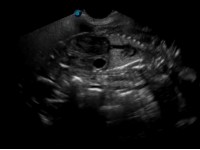

This week I cover a topic that it is fair to say has shaped the last few years of my life – namely, equine pregnancy. It is particularly topical given the launch of the new iScan which is perfect for advanced equine pregnancy work. Although previous articles have touched on this subject where I discussed my PhD in general, here I will discuss particular landmarks you should look out for during early equine pregnancy (day 120 of gestation).